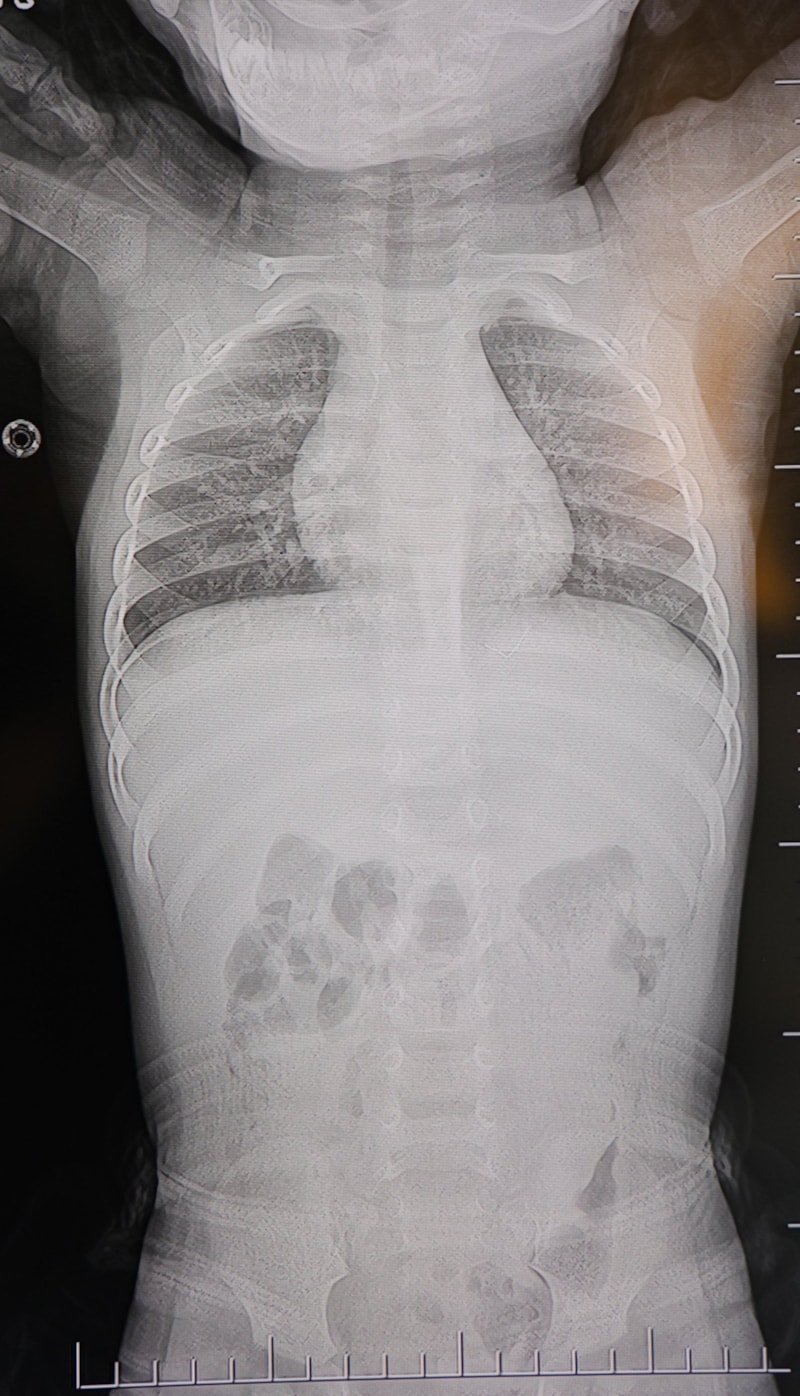

Baba Poyraz, bir gün acil serviste yapılan kontrollerde bebeğin belinde yabancı cisim olduğunu, çekilen filmlerde ise “L” şeklinde zımba teli tespit edildiğini söyledi.

Başhekim yardımcısının yönlendirmesiyle tomografi çekildi. O zaman belinde zımba teli olduğu netleşti. Başka bir hastaneye götürdük, ‘riskli, 8 yaşına kadar alınamaz’ dediler, geri gönderdiler. Eve geldikten üç gün sonra oğlum bayıldı. Kardeşimle özel hastaneye götürdük. Orada filmlere baktılar, ‘akciğere doğru gidiyor, L şeklinde zımba teli var, alınması lazım’ dediler” dedi.